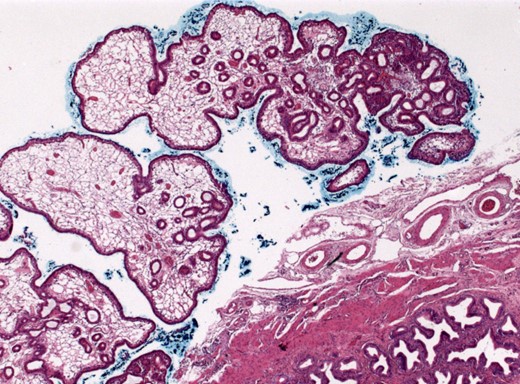

Three months later, the patient had exacerbation of the right lower quadrant pain. At this time, the pain was accompanied by fever and diarrhea appearing 4 days ago. Leukocyte count was still normal; CRP was slightly elevated (3.5 mg/dl). Repeated CT scan showed an increase in wall thickness of the vermiform appendix with mild surrounding reaction according to acute signs of inflammatory disease. A diagnostic laparoscopy with cholecystectomy and appendectomy was performed using standard four-port position for laparoscopic cholecystectomy [7] with only one additional incision (10-mm port) in the left lower quadrant for appendectomy. Intraoperatively, the appendix was suspicious and thickened. Pathologic analysis demonstrated one small appendiceal diverticula with inflammation (Fig. 1). The gallbladder showed a small tubular adenoma with low-grade dysplasia (Figs 2 and 3). The patient recovered well and was discharged 3 days later.

We thank Prof. Dr med. F. Fend and PD Dr med. P. Adam from the Department of Pathology and Pathological Anatomy for providing histological images and histopathological expert advice.